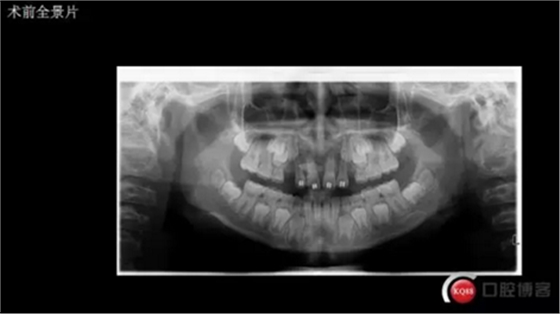

三年半前,家長(zhǎng)領(lǐng)著小孩前來(lái)要求矯正牙齒,男,約八歲,兩中切牙間隙約12MM,有一多生牙,全景片顯示深處還橫著一顆,也許正處叛逆期,小孩非常的調(diào)皮,經(jīng)過(guò)幾次的各種哄和商談,也可能為了好看,終于勉強(qiáng)同意先拔掉露出的多生牙,前牙片斷弓關(guān)閉間隙

CBCT術(shù)前分析,精準(zhǔn)找到牙齒的具體位置